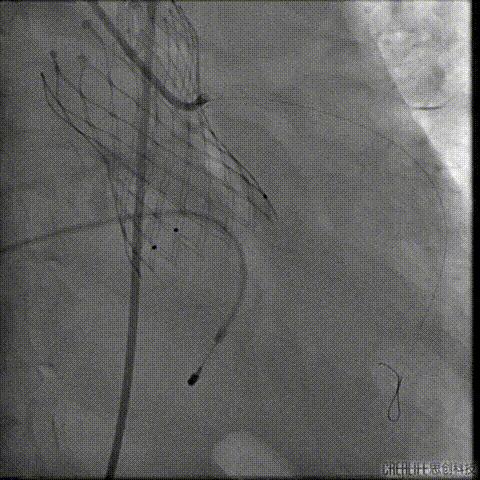

经瓣架网眼挂上指引管

反复确认指引管经瓣架网眼

指引管经瓣架网眼

经网眼置入导丝

置入4.0mm*23mm微创冠脉支架

定位并释放支架

退出球囊扩张突入瓣架部位

复查冠脉造影

多体位复查冠脉造影